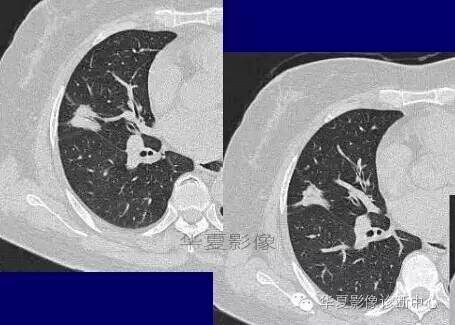

磨玻璃结节良恶性影像分析策略磨玻璃结节良恶性影像分析策略 这个按常规看到血管由凹陷处进去常规95%考虑癌,可是这里却不是

除非说这里GGO边缘稍模糊一些

宽基底与胸膜相连

近端有模糊的高密度影